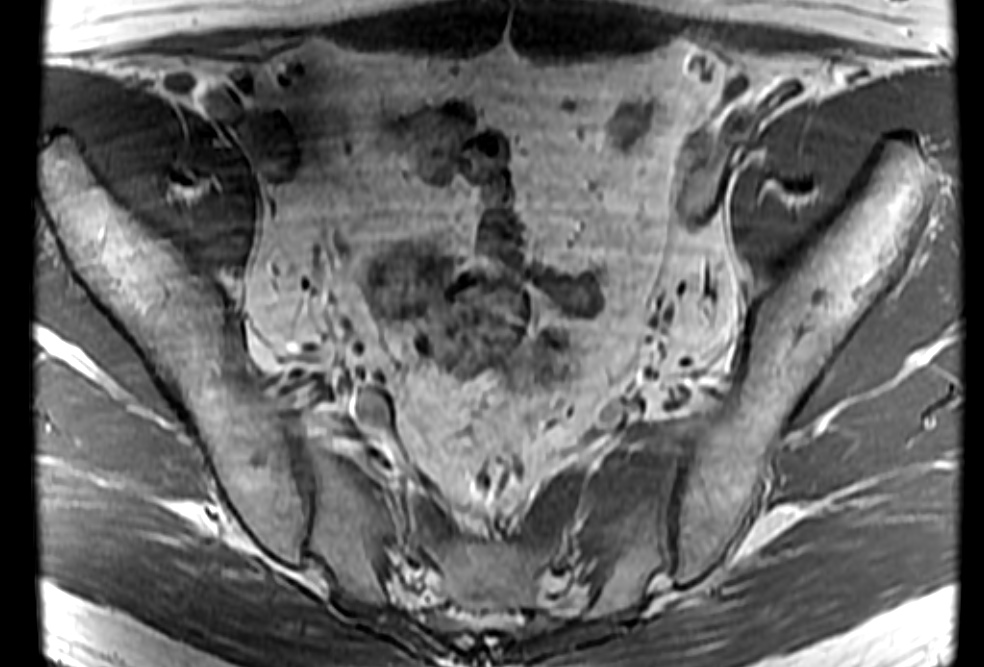

Bilateral sciatica

Bilateral accessory piriformis muscles at the S2 level attaching to the sacral body, anterior the S2 nerve roots. Normal piriformis muscles should be posterior to the sacral nerve roots. The result is that the S2 nerve roots may be pinched between the piriformis and accessory piriformis muscles.

Bilateral accessory piriformis muscles